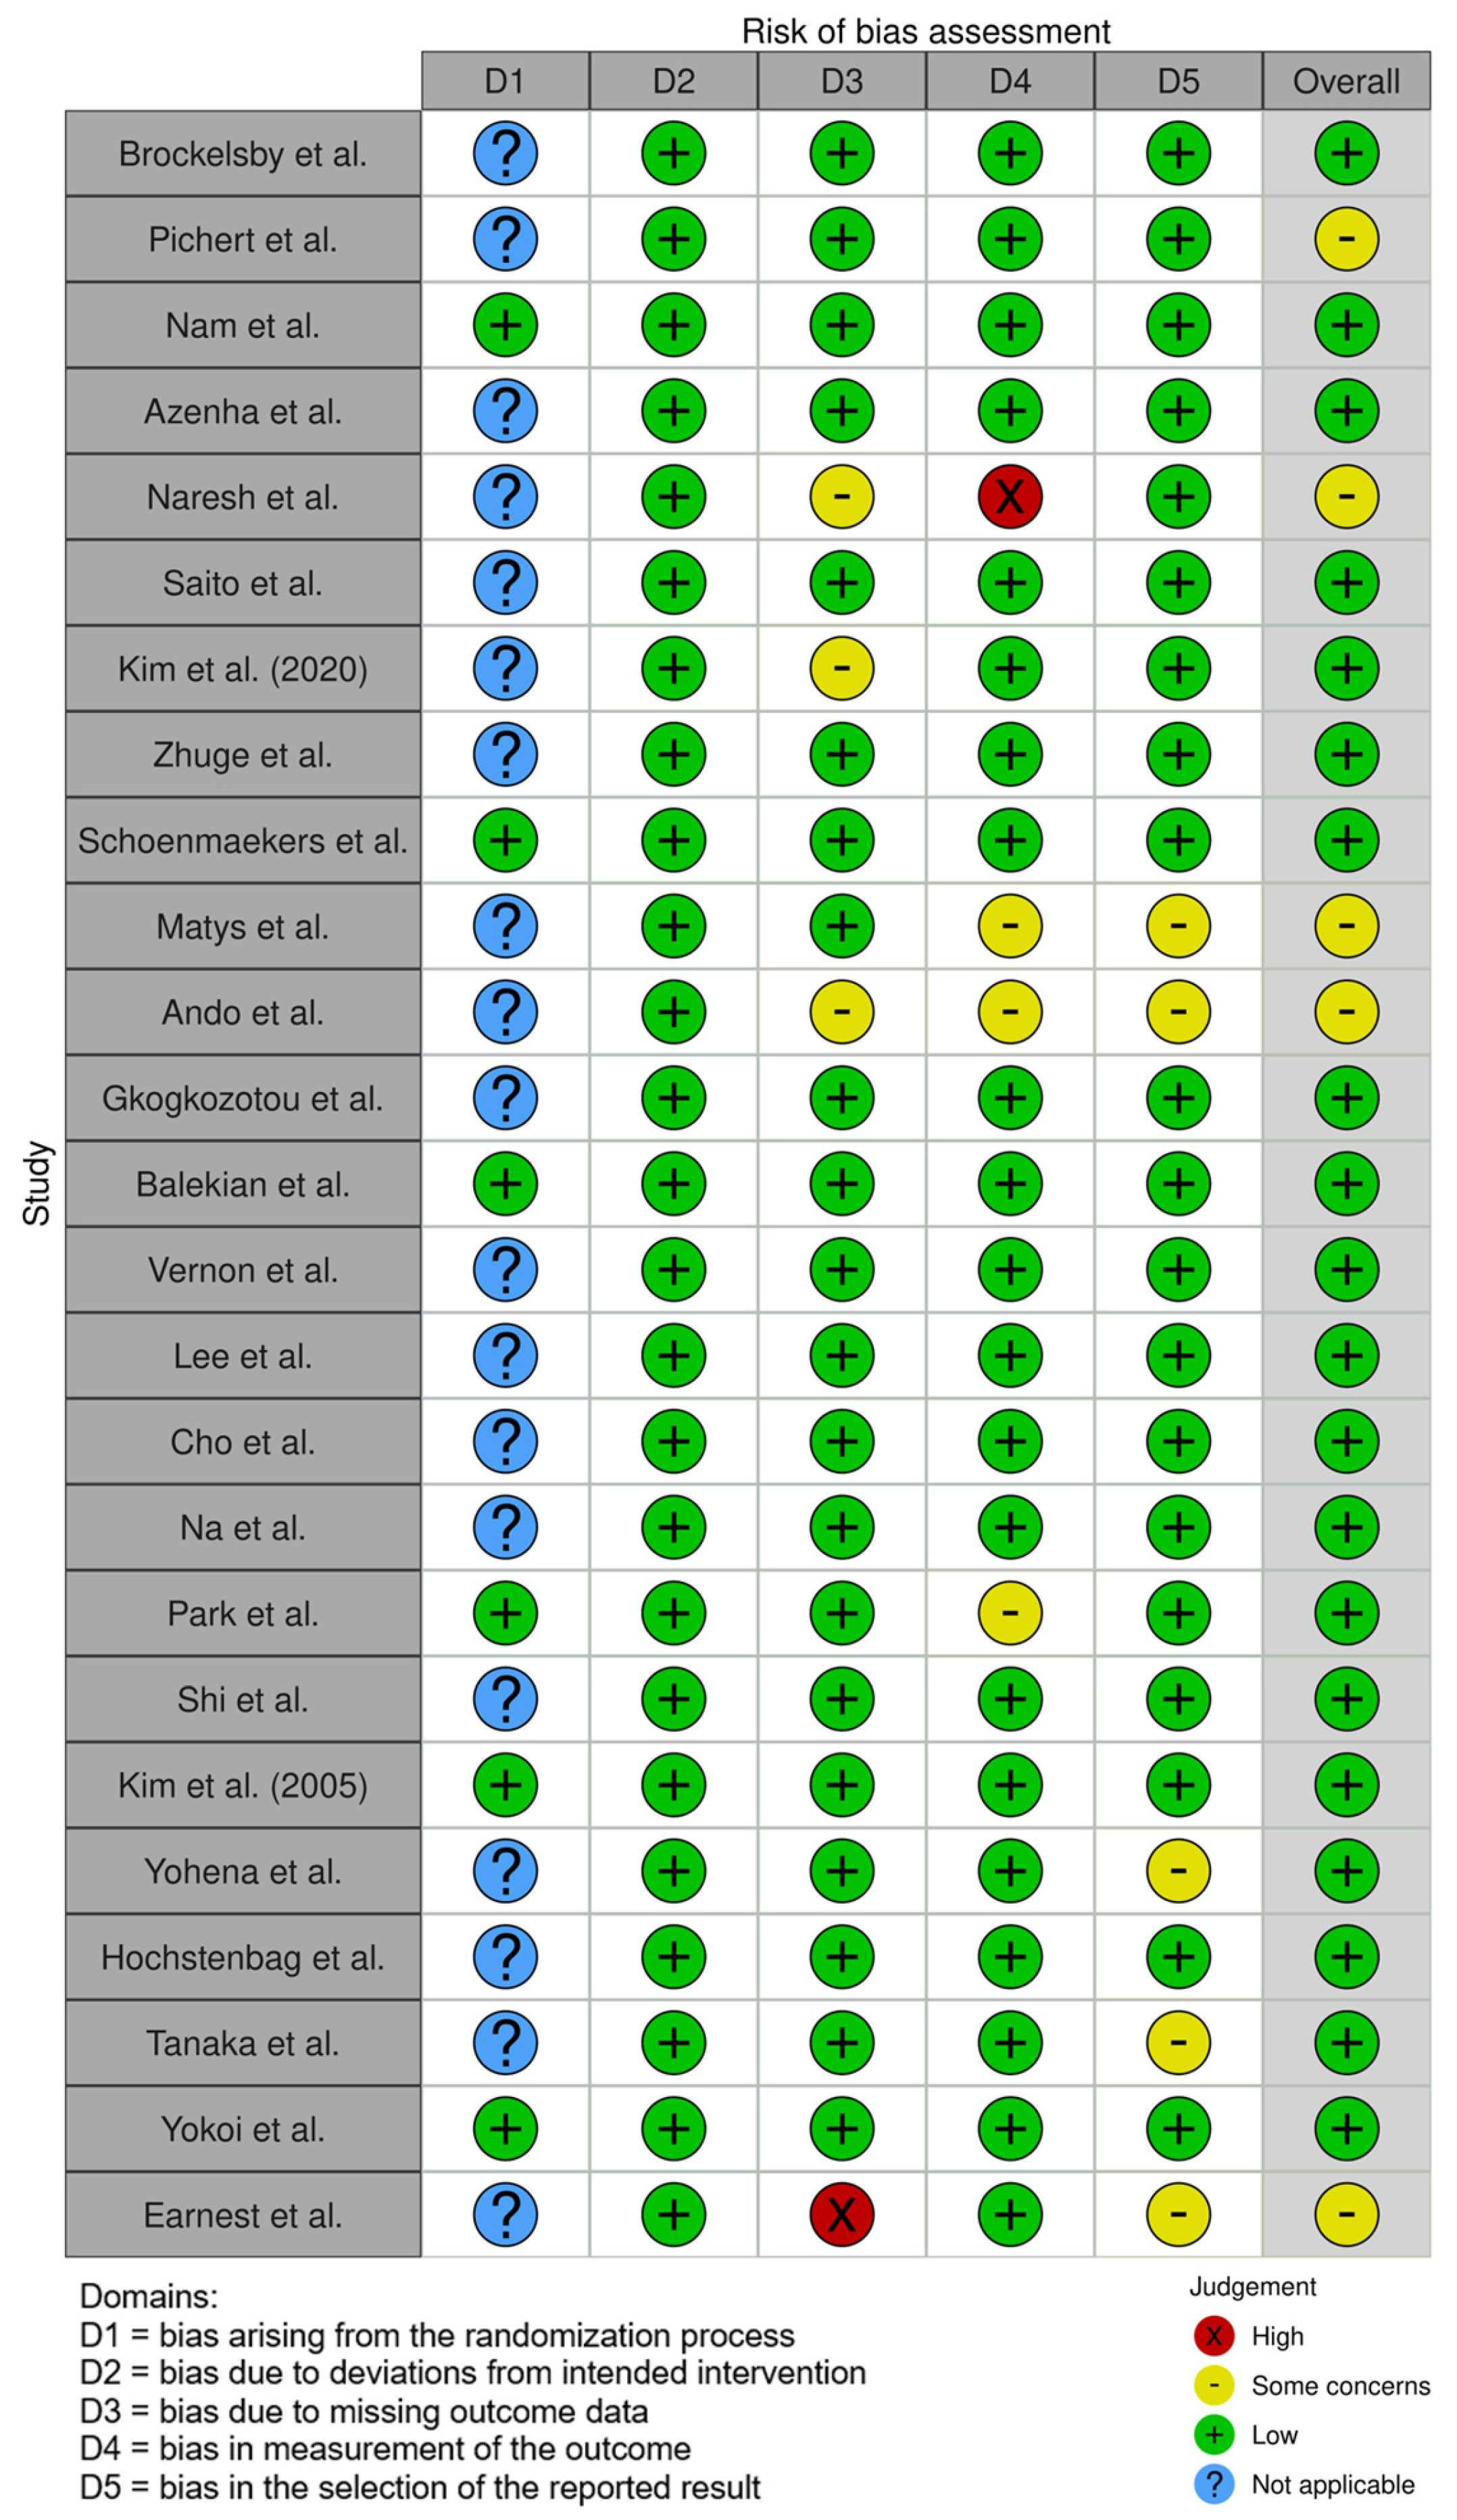

3.2. Risk of Bias Assessment